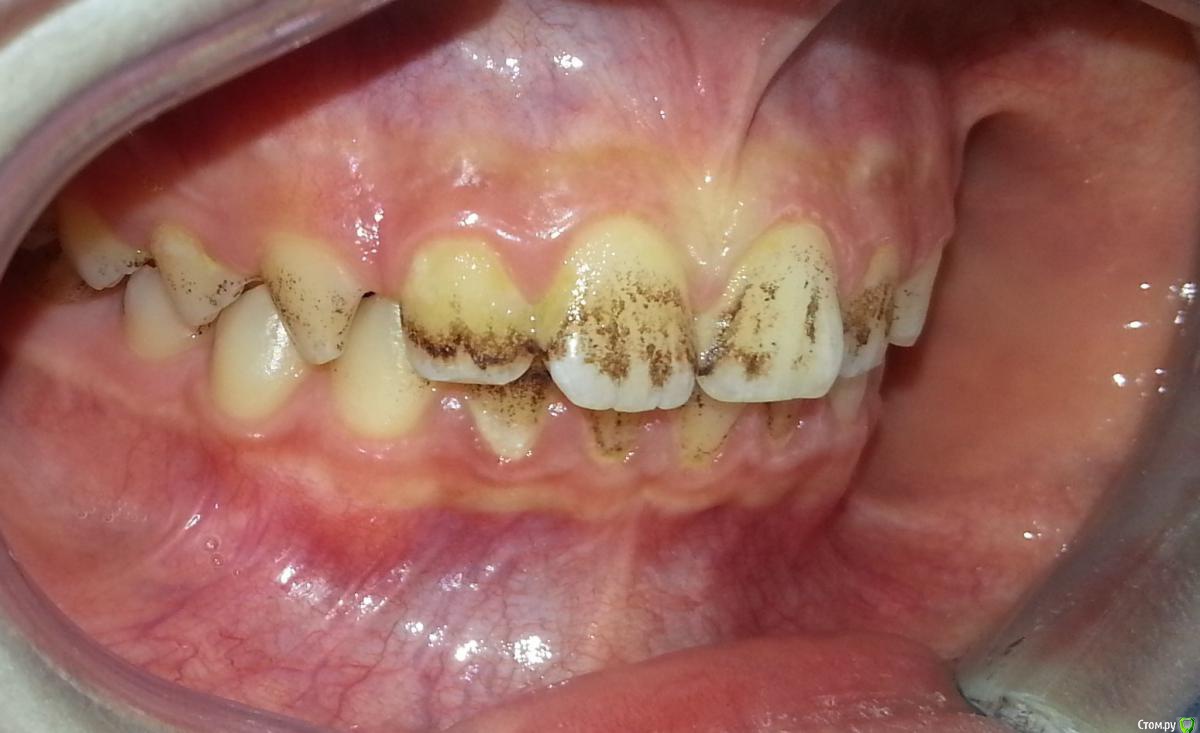

Nitrino1 Опубликовано 6 февраля, 2017 Поделиться Опубликовано 6 февраля, 2017 Здравствуйте коллеги, помогите с уточнением диагноза) Я не детский стоматолог, мамаша принесла ребенка заодно проконсультировать по поводу налета, посмотрел сфоткал) Первое что пришло на ум это налет Пристли)) Хотел уточнить) Жалоб нет, только эстетика..Убирали налет у стоматолога, через месяц все заново появилось.Буду благодарен если уточните как добиться постоянного эффекта.Ребенку 10 лет, мальчик Ссылка на комментарий

Петренкуся Опубликовано 15 февраля, 2017 Поделиться Опубликовано 15 февраля, 2017 Если причина ЖКТ или кровь, то излечите соматику,не будет появляться.А если причина не в этом, то придётся надеяться на "перерастёт" (я имею в виду период полового созревания) Ссылка на комментарий

Петренкуся Опубликовано 22 марта, 2017 Поделиться Опубликовано 22 марта, 2017 Сейчас на приёме была девочка 8 лет, клиника один в один с Вашим пациентом. Родители обследовали ее с головы до ног, нашли хеликобактер, всё остальное в норме. Пролечили, сегодня повторная гигиена, налёт снимается легче. Теперь будем ждать отдаленный результат. А какой результат у Вас? Ссылка на комментарий

Петренкуся Опубликовано 1 июня, 2017 Поделиться Опубликовано 1 июня, 2017 Хеликобактер оказался ни при чем. Сегодня позвонили родители, сказали , что налёт благополучно вернулся( я просила сообщить отдалённый результат). Теперь у девочки обнаружили гиповитаминоз vit D, будут лечить, результат обещали сообщить, а пока чистим. 1 Ссылка на комментарий